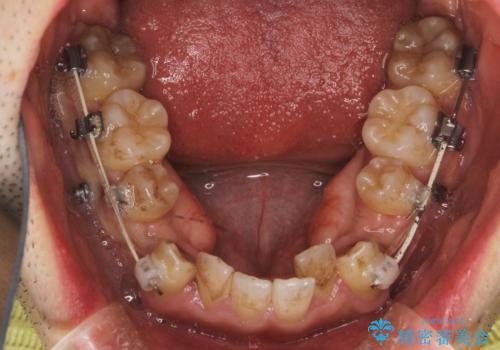

途中までは下顎は全体にワイヤーをはらずに、セクショナルワイヤーにて治療を進めています。

上顎は最初から全体にワイヤーをはっていましたが、上顎前歯部の歯肉退縮のリスクが高そうだったために、途中まで下顎と同じくセクショナルワイヤーで進めています。

- ワイヤー 審美装置

- 2年6ヶ月